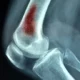

Cuando el hueso forma parte de una articulación móvil, que también se conoce como articulación sinovial, se presenta cartílago hialino. El cartílago hialino es un tipo de cartílago articular que recubre las superficies articulares de los huesos dentro de la articulación. Su característica principal es su superficie lisa y elástica, que reduce la fricción y permite el movimiento suave de los huesos en la articulación. Además, actúa como amortiguador, absorbiendo impactos y distribuyendo las fuerzas de manera uniforme, contribuyendo así a la salud y la funcionalidad de la articulación.

La habilidad del hueso para llevar a cabo su función esquelética se atribuye a varios elementos. En primer lugar, el tejido óseo, que proporciona la estructura y la resistencia necesarias para el soporte del cuerpo y la protección de órganos vitales. Los ligamentos, que son bandas fuertes de tejido conectivo, desempeñan un papel crucial al conectar los huesos entre sí, proporcionando estabilidad y limitando el rango de movimiento de las articulaciones. En el caso de una articulación móvil, el cartílago articular, específicamente el cartílago hialino, es esencial. Actúa como una interfaz lubricada que facilita el movimiento suave entre los extremos óseos, contribuyendo así a la funcionalidad y la longevidad de la articulación.